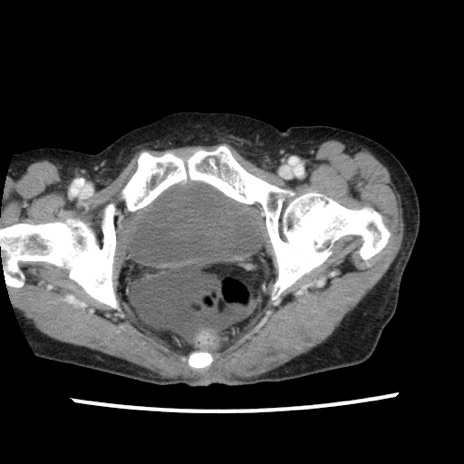

矢状断像

【症例】80歳代女性

【主訴】腹痛

【現病歴】8時間前から腹痛あり来院。

【既往歴】糖尿病、脂質異常症、子宮体癌にて子宮全摘術

【身体所見】意識清明・会話良好だが腹痛で苦悶様、全腹部にわたって反跳痛と圧痛あり

【データ】WBC 13600、CRP 0.14、LDH 224、CK 90